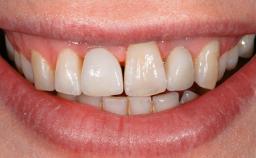

This case describes the ongoing management of a 64-year-old healthy, non-smoking female patient with erosive oral lichen planus (OLP) affecting the gingivae and the buccal and lingual mucosa. The peri-implant mucosa was also affected subsequent to implant placement. The patient had osseointegrated implants (four in the maxilla, four in the mandible) placed following extraction of hopeless teeth and a healing period. The patient had a history of OLP prior to implant placement and had been referred to an oral-medicine specialist for definitive diagnosis and treatment. She exhibited generalized oral mucosal involvement. Following a clinical assessment, biopsy, and blood tests, she was treated with topical corticosteroids. Systemic prednisolone was reserved for severe flare-ups. Amphotericin lozenges were used in combination with corticosteroid treatment to prevent the development of oral candidiasis.